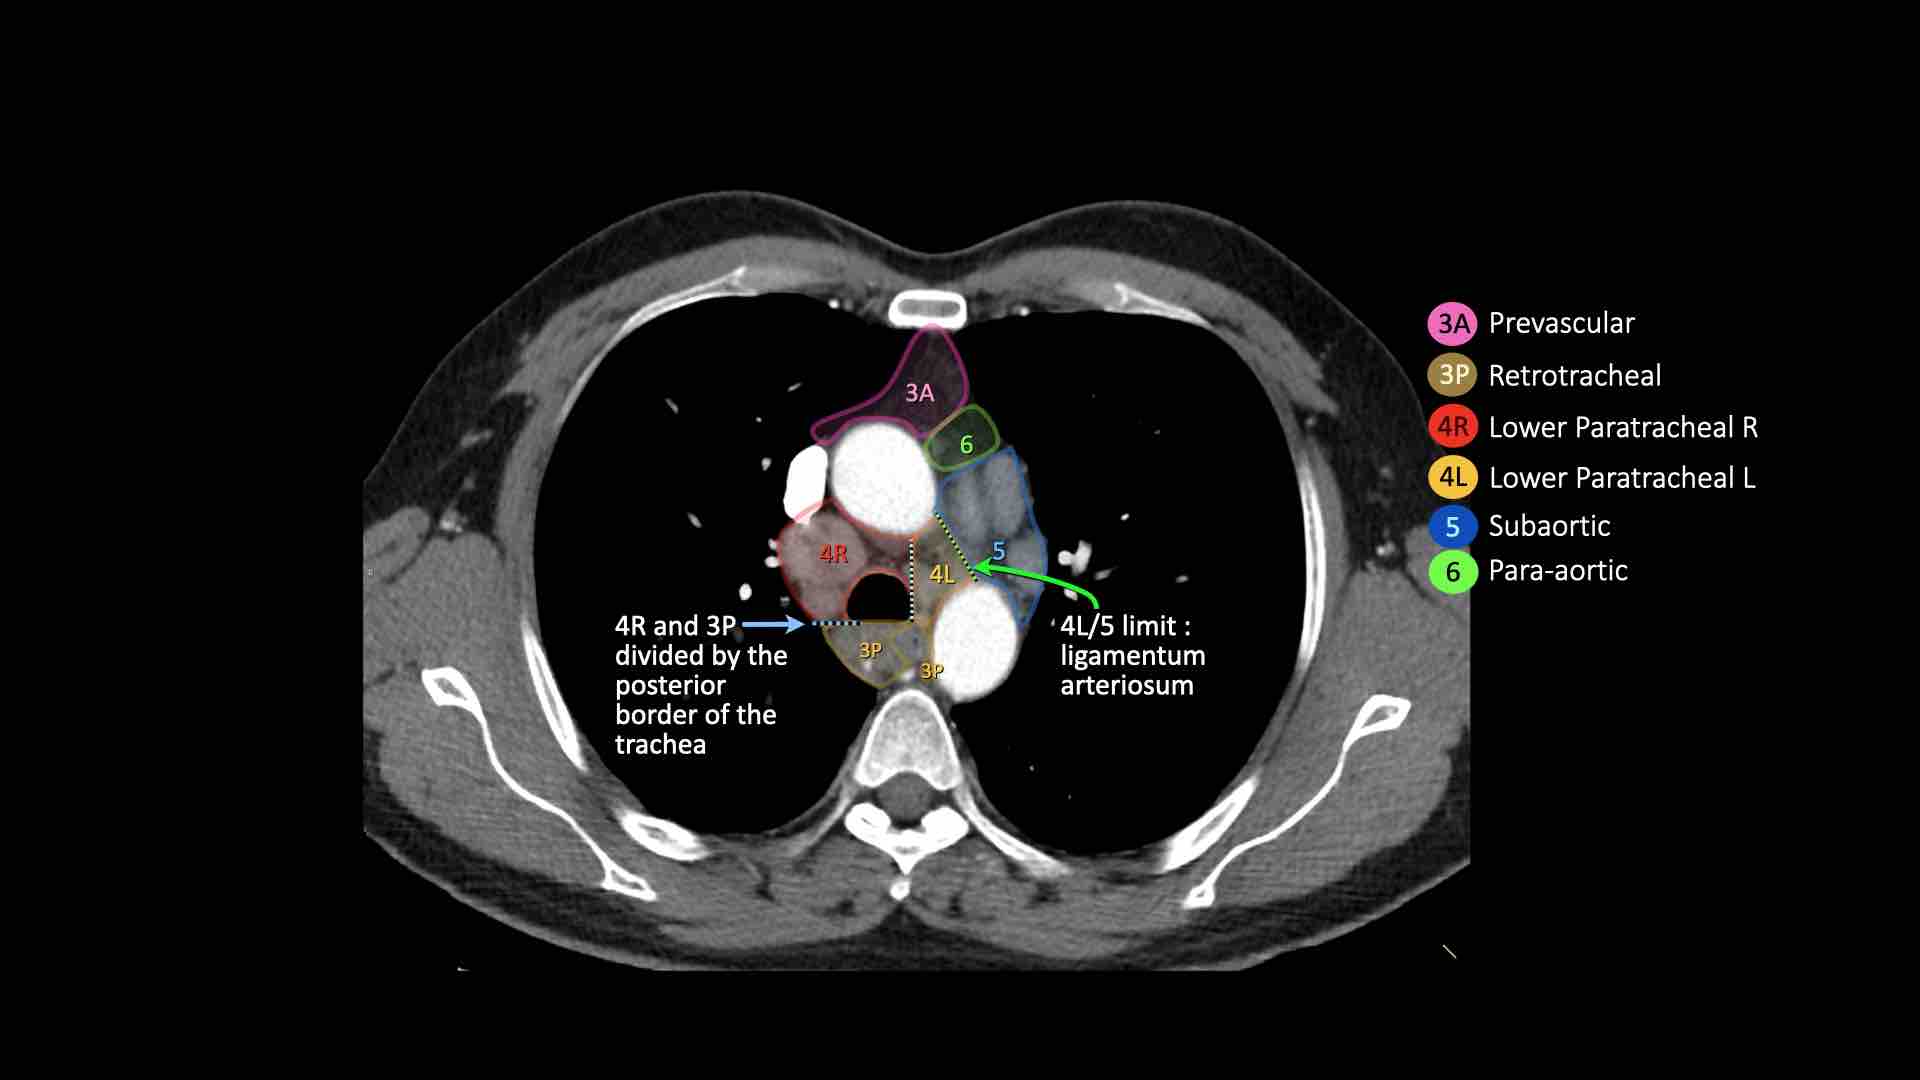

4L. Hạch cạnh khí quản dưới bên trái

Hạch nhóm 4L là các hạch cạnh khí quản dưới nằm bên trái bờ trái của khí quản, giữa đường nằm ngang tiếp tuyến với bờ trên quai động mạch chủ và đường tiếp tuyến với bờ trên động mạch phổi trái.

Nhóm này bao gồm các hạch cạnh khí quản nằm ở phía trong dây chằng động mạch.

Hạch nhóm 5 (cửa sổ phế động mạch) nằm ở phía ngoài dây chằng động mạch.

Bên trái là hình ảnh ngay trên mức thân động mạch phổi, cho thấy các hạch cạnh khí quản dưới bên trái và bên phải.

Ngoài ra còn có các hạch nhóm 3 và nhóm 5.

Bên trái là hình ảnh ở mức phần dưới khí quản, ngay trên carina.

Bên trái khí quản là các hạch 4L.

Lưu ý rằng các hạch 4L này nằm giữa thân động mạch phổi và động mạch chủ, nhưng không nằm trong cửa sổ phế động mạch, vì chúng nằm ở phía trong dây chằng động mạch.

Hạch nằm bên ngoài thân động mạch phổi là hạch nhóm 5.

5. Hạch dưới động mạch chủ

Hạch dưới động mạch chủ hay hạch cửa sổ phế động mạch nằm ở phía ngoài dây chằng động mạch hoặc động mạch chủ hoặc động mạch phổi trái, ở đoạn gần trước nhánh đầu tiên của động mạch phổi trái, và nằm trong bao màng phổi trung thất.

6. Hạch cạnh động mạch chủ

Hạch cạnh động mạch chủ (động mạch chủ lên hoặc cơ hoành) nằm ở phía trước và bên ngoài động mạch chủ lên và quai động mạch chủ, từ bờ trên đến bờ dưới của quai động mạch chủ.